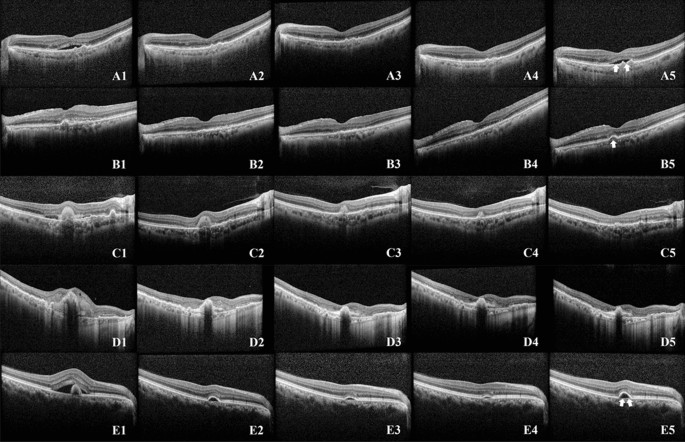

Predicting a recurrence within a 3-month timeframe following three loading injections is a challenging task. Both human specialists and AI model showed limited ability to accurately predict outcomes based just on a single pre-treatment OCT image, resulting in almost random results. However, the accuracy of the prediction showed an improvement when assessed using the OCT images taken after the first, second, and third consecutive injections. This improvement was observed not only among human experts but also in the AI model. A trend was observed that eyes that exhibit favorable response following a single injection likely to showed lower recurrence and remained as dry macula. Examining the heatmap highlighted by the AI model, it is evident that the AI focuses on areas with significant changes, such as SRF, IRF, and SHRM. This observation suggests that the AI is making accurate assessments, eliminating the need for separate learning of individual lesions (Fig. 2). However, this pattern did not apply to patients who developed a minor SRF or a small increase in PED within 3 months after loadings injections. Conversely, there was a gradual decrease in fluid over the three loading injections for some patients, and these individuals did not experience another relapse for a maximum of 3 months. Figure 3 showed the cases that the AI model provided a false prediction. To emphasize, predicting a relapse within a specific period after three loading injections is a challenging task, and to the best of our knowledge, our study is the first to attempt such a prediction.

Cases that the AI model provided a false prediction. A1, B1, C1, D1, E1 were taken before first injection, A2, B2, C2, D2, E2 were taken 1 month after first injection, A3, B3, C3, D3, E3 were 1 months after second loading injections, A4, B4, C4, D4, E4 were taken 1 months after three loading injections, and A5, B5, C5, D5, E5 were taken 4 month after the three loading injections. OCT after the first injection showed a favorable outcome (A2 and B2), however within 3 months after loading injections the SRF reappeared (A5, arrow), or the PED reappeared (B5 and arrow); SHRM decreased gradually over the three loading injections, but almost all SHRM disappeared (C5), or no recurrence was observed (D5); the OCT showed only some PED after three loading injections (E4), but the increased PED proved to be a recurrence (E5); all of the above cases that the AI model wrongly predicted.